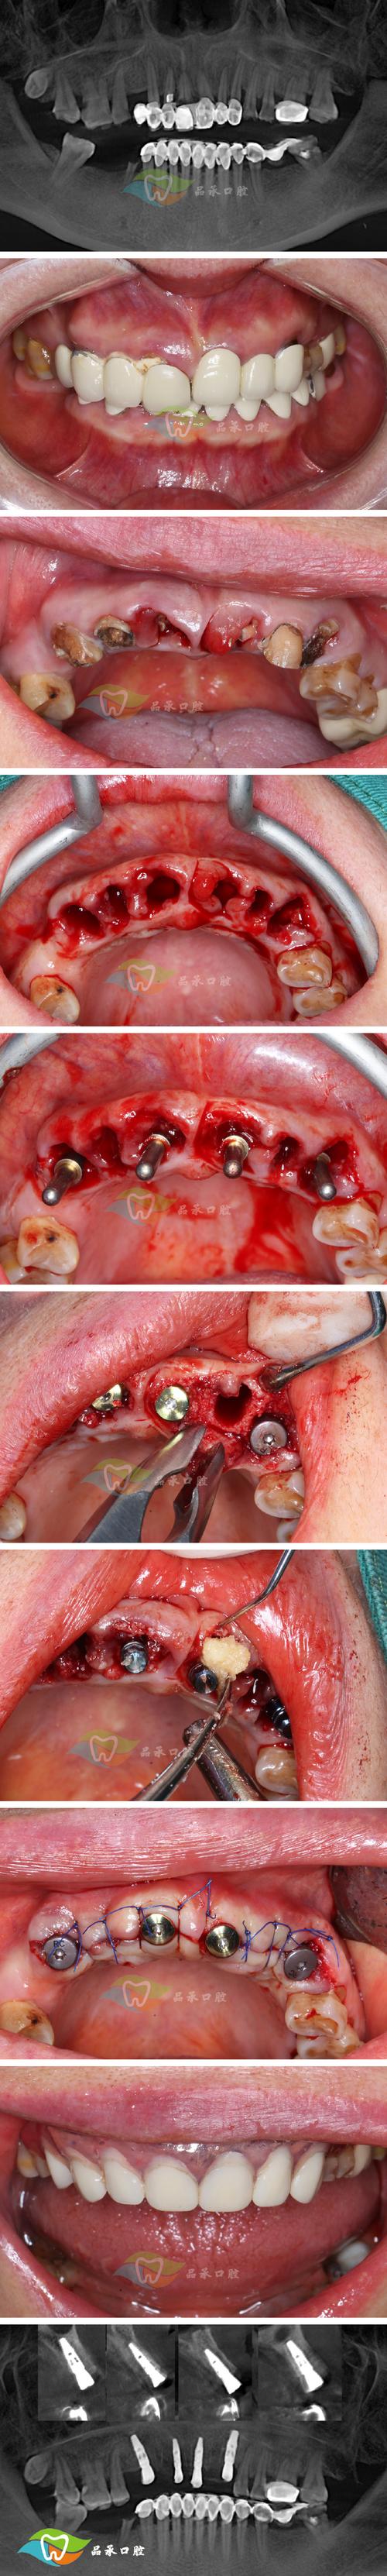

- 检查评估: 牙医检查你的口腔,确定是否适合种植,以及缺失牙位置的骨头情况。

- 处理患牙(如果需要): 如果要拔的牙本身有严重问题(如根尖脓肿),先做根管治疗(杀神经)。

- 拔牙: 拔除需要被替换的坏牙。

- (可能)植骨: 如果骨头不够,可能需要植骨。

- 植入种植体: 手术将种植体植入牙槽骨。

- 愈合期: 等待种植体与骨头牢固结合(骨结合,通常需要3-6个月)。

- 安装基台和牙冠: 在愈合好的种植体上安装基台,再安装牙冠,完成种植牙。